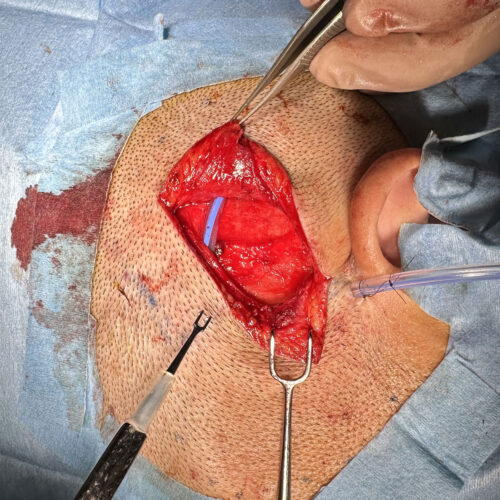

手術前

直線で切開すると傷跡が目立つことがあるので、ジグザクで切開します。ジグザクで切開すると創部が展開しやすい。

術中所見①

脂肪腫を丸ごと完全に取り出し、その下にはドレーンと言って管を挿入留置します。